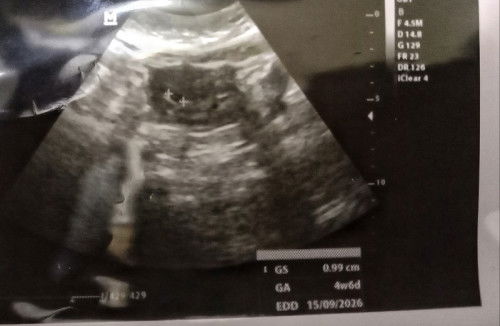

Saya kan haid terakhir itu bln maret thn 2025 posisi saya masih kb suntik 1 bln. Nah bln april 2025 saya lepas kb (itu sdh 1 thn saya kb suntik 1 bln) dan gk haid terus selama thn ini 2026 januari. Tiba2 tgl 6 Januari 2026 saya merasa kram seperti mau haid, iseng2lah tgl 7 aku tespek eh positif jelas bnget, akhirnya tgl 12 Januari 2026 saya usg lah, ternyata usia kandungan ku masih kecil masih 4w6d. Bulan dpn usg lagi buat kontrol untuk memastikan apakah dia berkembang atau tidak. Pertanyaan ku kok bisa ya gk haid lama tp hasil positif, kira2 berkembang gk ya dan kelak bayiku ini gk knp2 kan? Adakah yg punya pengalaman yg sama? Kalau boleh sharing dong krn kejadian ini pertama kali bagiku. Terimakasih.. (Saya sebelumnya sdh punya anak 1 dan pernah keguguran juga anak kedua, jadi skrg anak ke 3) #mohonbantujawabbunda #Sharingdong_Bund #sharing